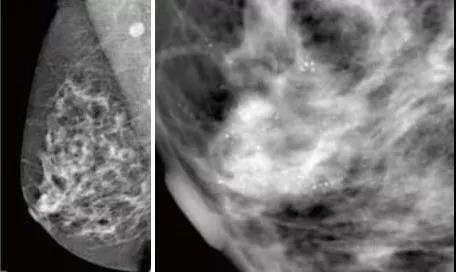

GE 平板數字乳腺機拍攝的右乳MLO,清晰顯示早期乳腺癌的沙粒樣鈣化,

此時乳腺觸診并沒有任何異常